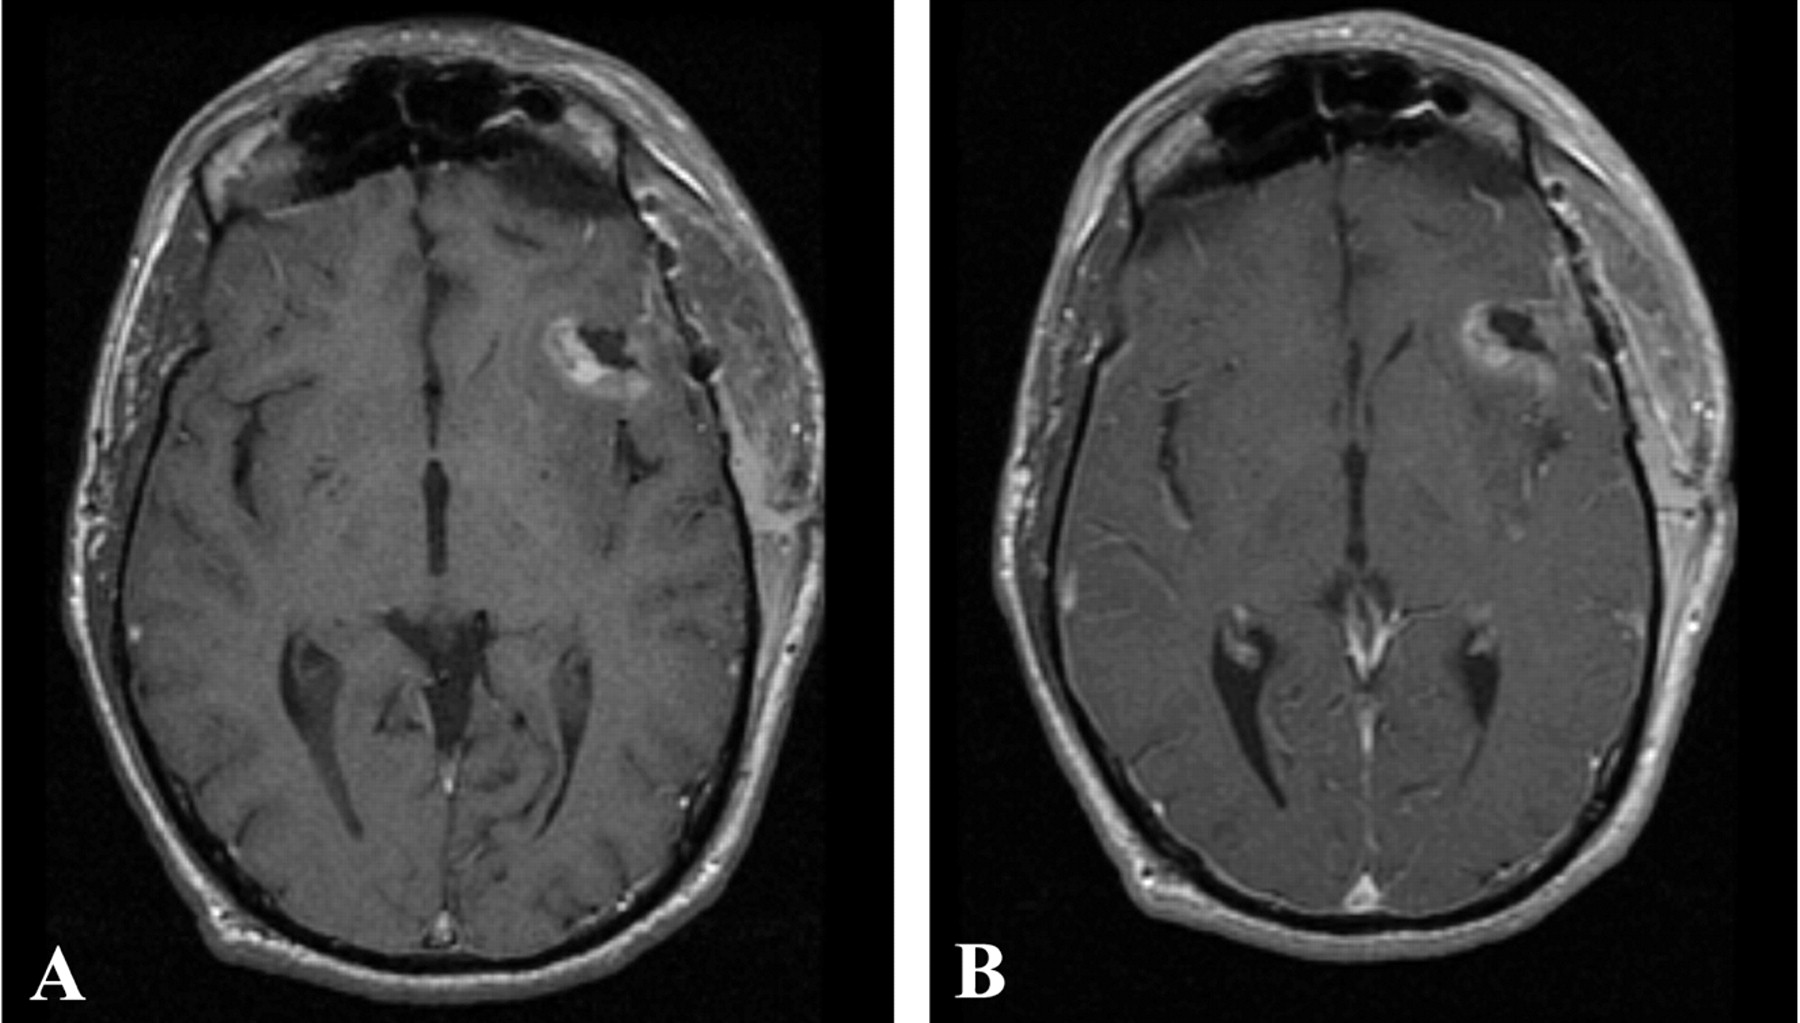

Both patients underwent IMRI-guided resection of their tumors. Preoperative MR imaging demonstrated the targeted lesion. Intraoperative MR without gadolinium, following the prior administration of ferumoxtran-10, easily provided images that demonstrated the lesions seen on preoperative MR images obtained in both patient 1 (Fig 1) and patient 2 (Fig 2). In one operation, post-resection imaging revealed a persistently enhancing area that was then resected (Fig 3). Even in the low-field-strength IMRI system, ferumoxtran-10 provided adequate imaging of the lesions in both of these patients. Postoperative MR images obtained in both patients had no significant enhancement with gadolinium, which suggests resection of the enhancing tumor bulk (Figs 4 and 5). Both postoperative MRIs show high T1 signal intensity in the wall of the resection cavity. The walls of the cavities, however, do not appear to enhance significantly with gadolinium. Figure 5 also shows the resection cavity itself filled with T1 hyperintense material. The cause of this residual T1 hyperintensity, either from blood or ferumoxtran, is unclear. Iron staining of one patient’s lesion demonstrated iron accumulation within peritumoral reactive cells (Fig 6).

Postoperative T1-weighted MR imaging from patient 2 performed 24 hours after surgery, without (A) and with (B) gadolinium. No significant gadolinium-enhancing areas are seen, although they may be masked by residual T1 signal intensity. These images demonstrate the difficulty with postoperative imaging in the face of blood products and hemostatic agents.